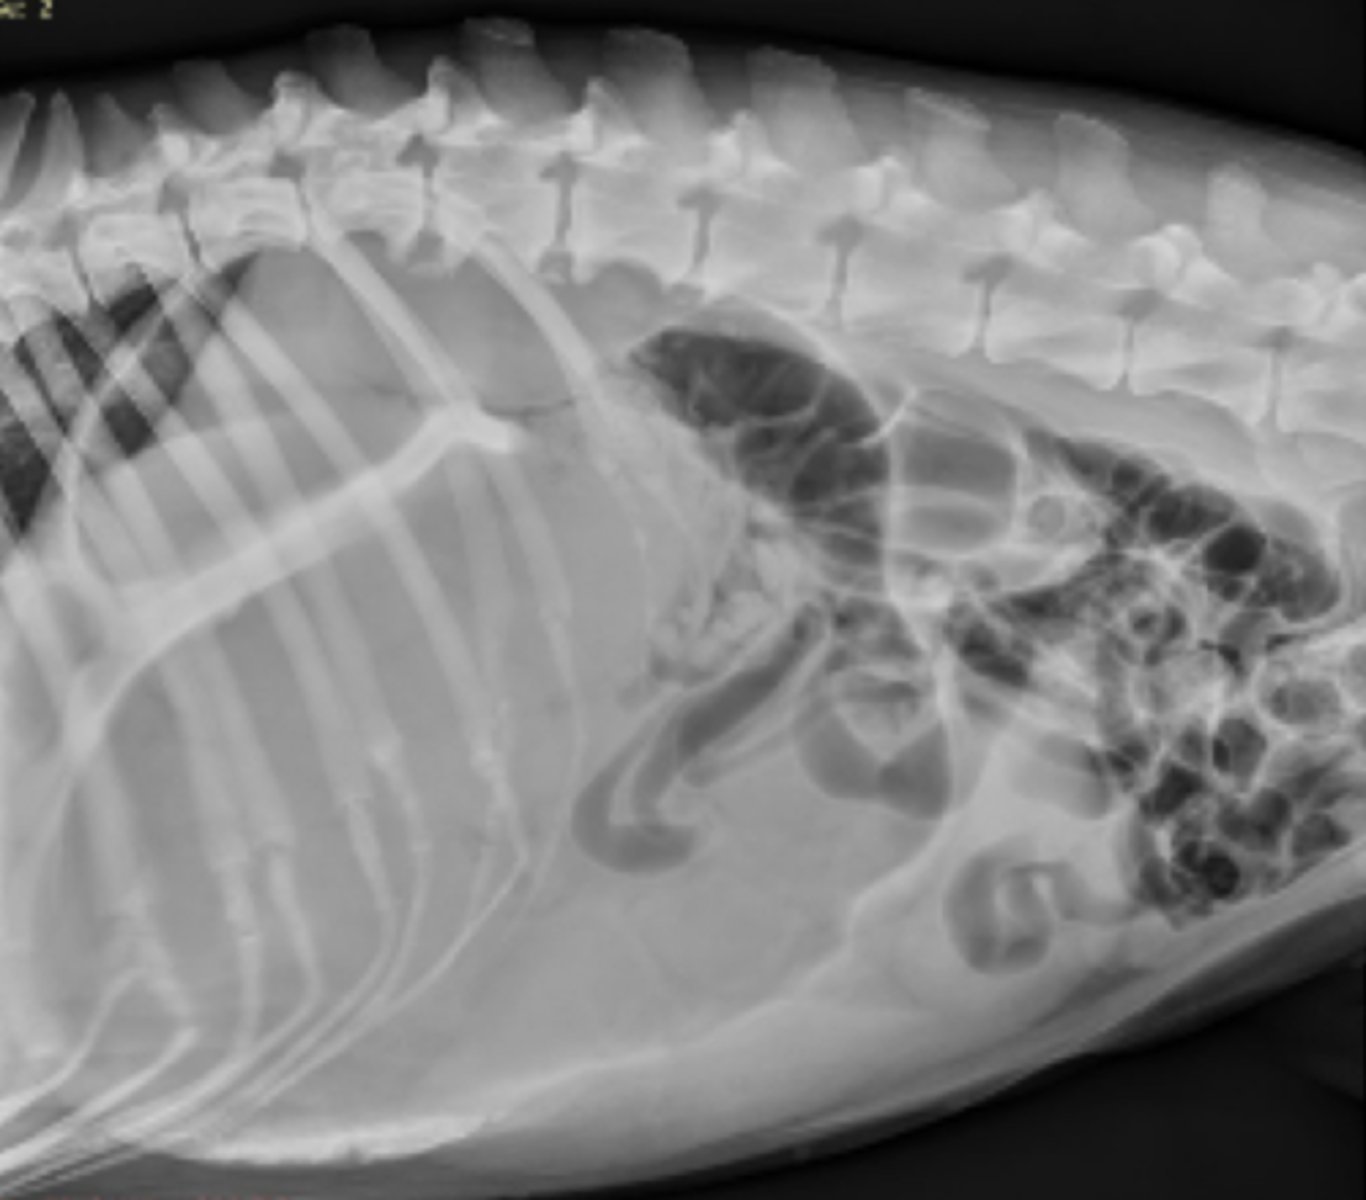

dilatación-torsión gástrica

patología: